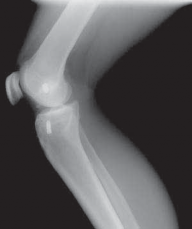

IMAGING AND OTHER DIAGNOSTIC STUDIES

3. Routine radiographs, including weight-bearing anteroposterior and lateral views as well as patellar views, should be performed. In the revision setting, these images allow for critical assesment of previous tunnel placement and assesment for possible bone loss at previous tunnels, which may require further evaluation and treatment.

1. Metallic fixation devices make previous tunnel placement easy to identify, but bioabsorbable screws and other types of fixation also can be evaluated for tunnel placement on these images (

FIG 1

).

2. These images also allow evaluation for possible evidence of osteoarthritis.

FIG 1 • A,B. Anterior cruciate ligament (ACL) reconstruction performed with an EndoButton (Smith & Nephew, Andover, MA) on the femur and staple fixation of the graft on the tibia. C,D. Anterior placement of the femoral tunnel in this primary ACL reconstruction performed with a two-incision technique. A B C

D

13. A common cause of failure related to surgical technique is anterior placement of a femoral tunnel, which often is detected on the lateral radiograph (

FIG 1D

).6,10 This may lead to tightening of the graft with knee flexion resulting in graft stretch-out or failure.